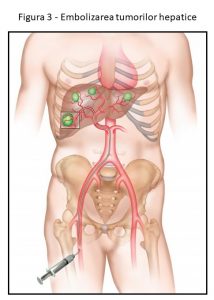

Ce este embolizarea tumorilor hepatice?

Embolizarea se referă la blocarea vaselor folosind o tehnică angiografică. Embolizarea este utilizată de radiologii intervenționali pentru a trata tumorile sau vasele anormale, prin introducerea unui cateter în zona inghinală și navigarea până la vasele care alimentează tumora în ficat.

În chimioembolizare, microsferele sau agenții lichizi încărcați cu agenți de chimioterapie, cum ar fi doxorubicină și irinotecan, sunt livrate angiografic la tumorile hepatice. În radioembolizare, microsferele radioactive, cum ar fi Yttrium-90, Holmium 166, sunt utilizate pentru a furniza o doză mare de radiații în interiorul tumorii, în timp ce țesutul sănătos din apropiere primește radiații minime. Tumorile hepatice primare și metastatice de dimensiuni mai mari și cu număr mai mare pot fi tratate prin embolizare.

Deși chimioembolizarea este relativ frecventă, radioembolizare este o procedură nouă care nu este disponibilă în majoritatea țărilor est-europene.